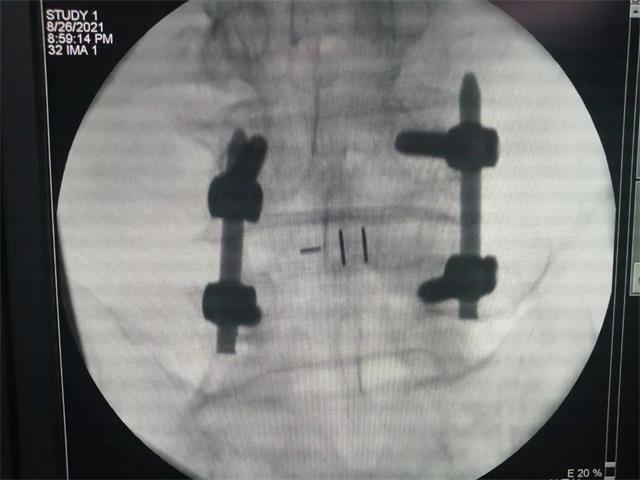

机器人经皮置钉

术后影像

术后切口(4个1.5—2厘米切口)

ULIF技术是科室继单侧双通道脊柱内镜技术(UBE)为患者解决腰椎管狭窄问题后的又一跨越性发展。该技术通过建立两个通道(一个视野通道,一个操作通道)进行手术操作,在UBE内镜辅助下完成中央椎管、双侧神经根及侧隐窝狭窄的减压,并在内镜下进行椎间植骨融合。仅在4个1.5—2厘米的切口内完成减压、融合、固定的操作,极大地减少了患者创伤,加速了患者的恢复速度。